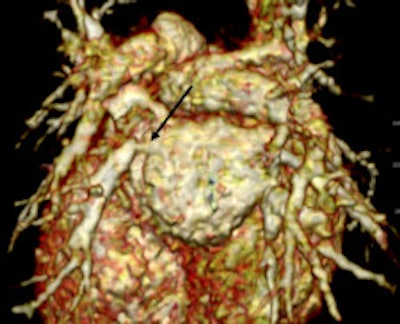

Retrospective ECG-gated study on a 5 year old with severe pulmonary hypertension. The CT images show dilated pulmonary arteries (top left). There is right atrial and ventricular dilatation with hypertrophy and bowing of the interventricular septum into the left ventricle (arrow, top right). There is abnormal arborization and angulation of the peripheral pulmonary arteries (top right, bottom), with multiple peripheral centrilobular nodules with perilesional ground-glass attenuation. Features are in keeping with pulmonary capillary hemangiomatosis.